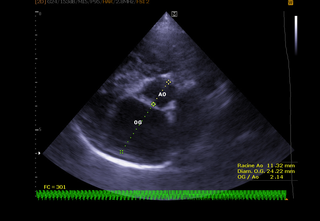

Photo Echographie cardiaque chez un chat Endoscopie digestive L'endoscopie permet une visualisation directe des lésions digestives ainsi que la réalisation de biopsies pour permettre d'établir un diagnostic Elle permet également une approche thérapeutique en particulier lors de retrait de corps étranger (œsophagien ou gastriqueLes signes de problème cardiaque chez le chat Au début on observe des signes de fatigue Puis, le plus souvent chez le chat, une gène respiratoire s'installe C'est l'insuffisance cardiaque gauche ou l'insuffisance cardiaque généralisée Si le cœur lâche brutalement, on aura un œdème aigu du poumon ou un épanchement pleuralPlusieurs gènes mais il n'existe qu'un test de dépistage pour un seul de ces gènes (HCM1) l'échographie cardiaque (en mesurant l'épaisseur des parois du coeur) est la seule façon de s'assurer que le chat n'est pas malade cet examen doit être renouvelé

Les Mesures En Echocardiographie 1 2 Centre Hospitalier Clinique Veterinaire Cordeliers A Meaux 77